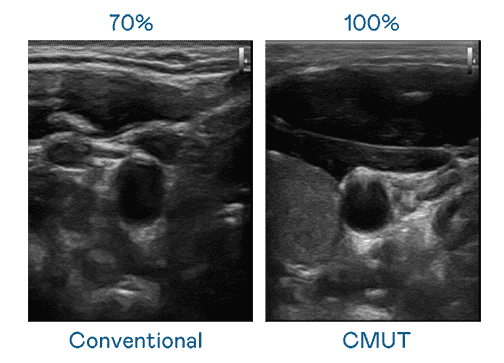

CMUT 技术是一种用电容式微机电元件来产生超音波讯号的技术。。与传统 PZT 压电式技术相比,,,CMUT 频宽增加 30%,,更宽频的超音波讯号让影像解析度大幅提升,,,,是实现高影像品质医疗超音波扫描、、促进精准医疗发展的关键技术。。。

超音波影像的解析度高低,,,,首先取决于探头能发出的讯号频宽。。。。尊时凯龙 CMUT 可提供高清晰的超音波讯号,,,,提供高频宽、、高灵敏度、、影像纹理细节更高的超音波影像,,协助医护人员缩短影像判读时间及利用精准的医疗影像进行诊断。。。。